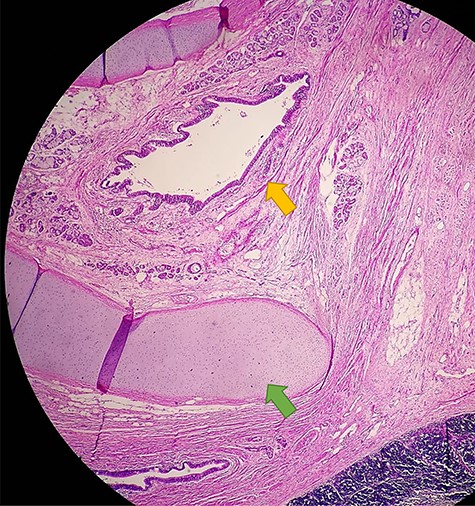

The patient underwent a total resection of the mediastinal mass via a median sternotomy. Given the extension of the teratoma and adhesions to the chest wall, an additional approach with a left anterior thoracotomy was made (Fig. 2). Entry into the pleural space was performed through the sixth intercostal space to obtain safe visualization of the cavity and proceed to tumor excision. Many adhesions were found to the thoracic wall, diaphragm and phrenic nerve. Additionally, a nutritional artery depending on left internal mammary artery was discovered with collateral veins draining to brachiocephalic vein. A section of the left internal mammary vessels, dissection of the phrenic nerve, ligation of the nutritional vessel, mediastinal tumor excision, ligation of the thymic vessels and thymectomy was performed. Thoracic drainage tubes (two) were placed. The mediastinal tumor, excised in block, was red–gray colored, well circumscribed and capsuled with a size of 15 × 15 × 20 cm. Postoperatively, the collapsed left lung was re-expanded, and the patient was extubated on Day 1 (Fig. 3). The patient recovered from the operation and was discharged on the ninth postoperative day. Preoperative atelectasis of the left lung partially resolved, and the pathological examination revealed a benign mature teratoma with cystic degeneration. Anatomical pathology test showed the presence of glandular epithelial cells concomitant with the presence of cartilage tissue (Fig. 4) The histochemistry test revealed CD3(+) CD20(+) TDT(−) CD5(−) cells. Thymic tissue was negative for malignancy; nine lymph nodes showed reactive follicular hyperplasia.

Anatomical pathology test showing the presence of glandular epithelial cells (yellow arrow) concomitant with the presence of cartilage tissue (green arrow)